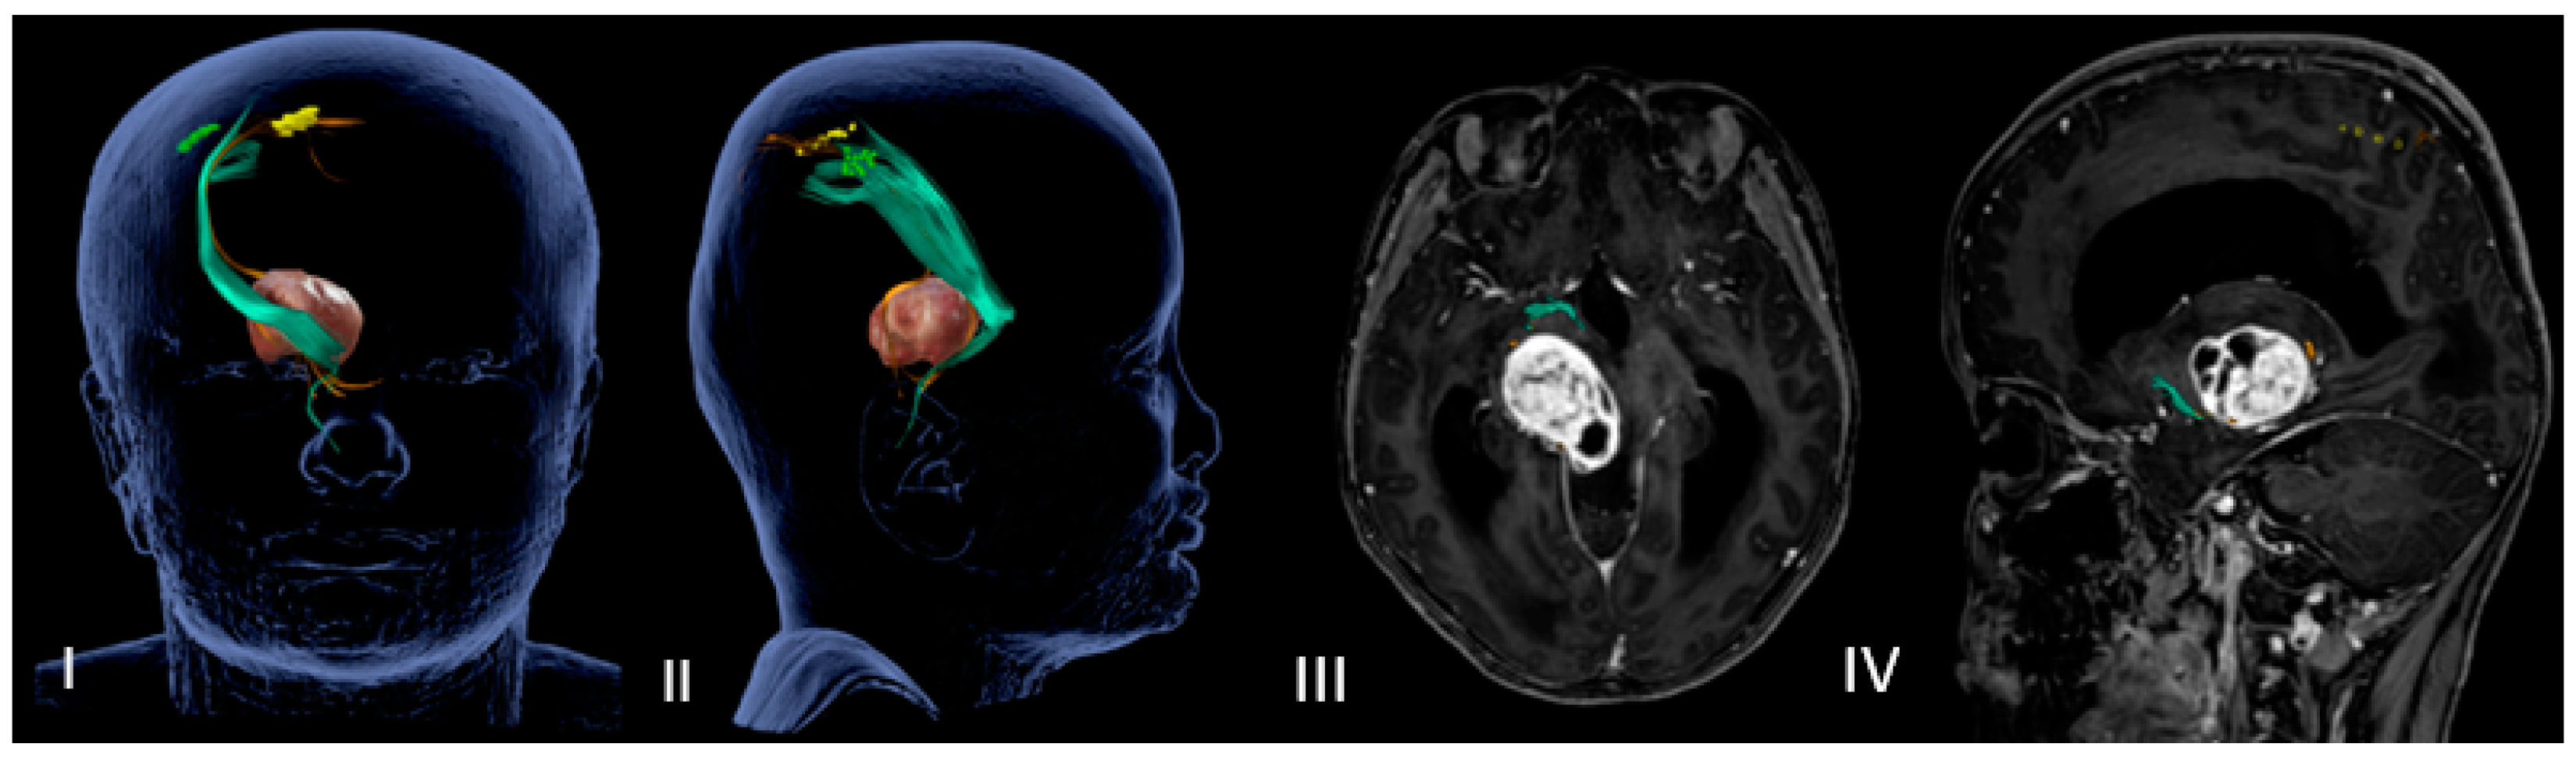

DTI-MRI CST reconstruction combined with nTMS mapping allows for an accurate tridimensional visualization of the cortical spinal bundles and helps the surgeon to choose the safer surgical corridor (Figure 1 and Figure 2).

Figure 1.

(I–IV) Neuronavigated transcranial magnetic stimulation pre-op study. (I,II) A 3D reconstruction of the nTMS data that shows cortical maps of the right spinal tract (CST) for the hand (green) and foot (yellow) and its relationship with the thalamopeduncular tumor of Case B. (III,IV): The brain MRI merged with the nTMS data shows that the cortical spinal tract (CST) runs antero-laterally with respect to a right thalamopeduncular tumor.

In the most recent cases (Case A–Case B), the preoperative nTMS was performed to obtain a cortical motor mapping and the cortical spinal bundles reconstruction. The nTMS data confirmed the DTI MRI data for the motor bundles’ displacement, adding functional information about cortical and subcortical motor areas of the mouth, arms and legs (Table 3).